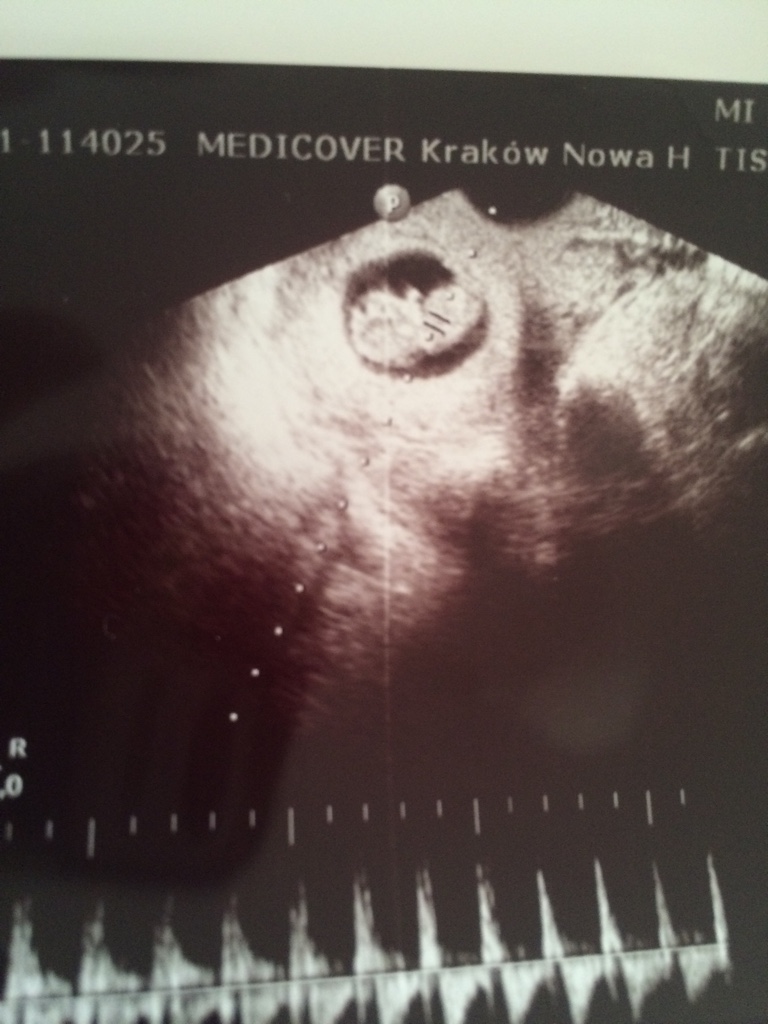

Druga próba. 6t6d, maluch ma ponad 1 cm. Serduszko pięknie bije.